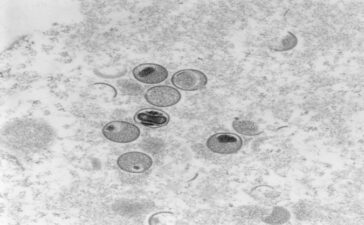

Sobe para 10 o número de casos notificados da varíola dos macacos aqui em Pesqueira

Boletim foi divulgado, nesta segunda (22), pela Secretaria Estadual de Saúde (SES-PE). Estado tem 258 casos em investigação, 19 conformações...

Especialistas em varíola do macaco avaliaram, nesta quinta-feira (21), se a Organização Mundial da Saúde (OMS) deve ou não declarar...